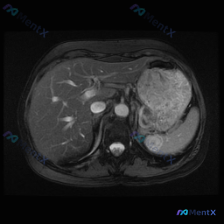

今天看到一个很有意思的影像分析场景,整理一下思路和大家分享。 先摆核心“矛盾”事实 预设前提是“观察脾脏病变”,但拿到的单幅腹部MRI T2加权轴位图像分析结果明确显示: - 肝脏、胆囊、胃腔、腹膜后大血管等结构均未见明确异常; - 脾脏:大小形态大致正常,实质信号均匀,未见明显的异常高或低信号灶。...

最近看到一份腹部CT的影像分析资料,觉得这个病例特别有警示意义,整理了一下思路和大家分享。 先看基础影像表现 这是一份横断面腹部增强CT(软组织窗)的结果: - 肝脏、双肾、胰腺:基本正常,肝脏实质密度均匀,双肾皮髓质分界清,胰腺边界清晰,腹主动脉壁有点状钙化(年龄相关可能); - 脾脏本身:大小、...